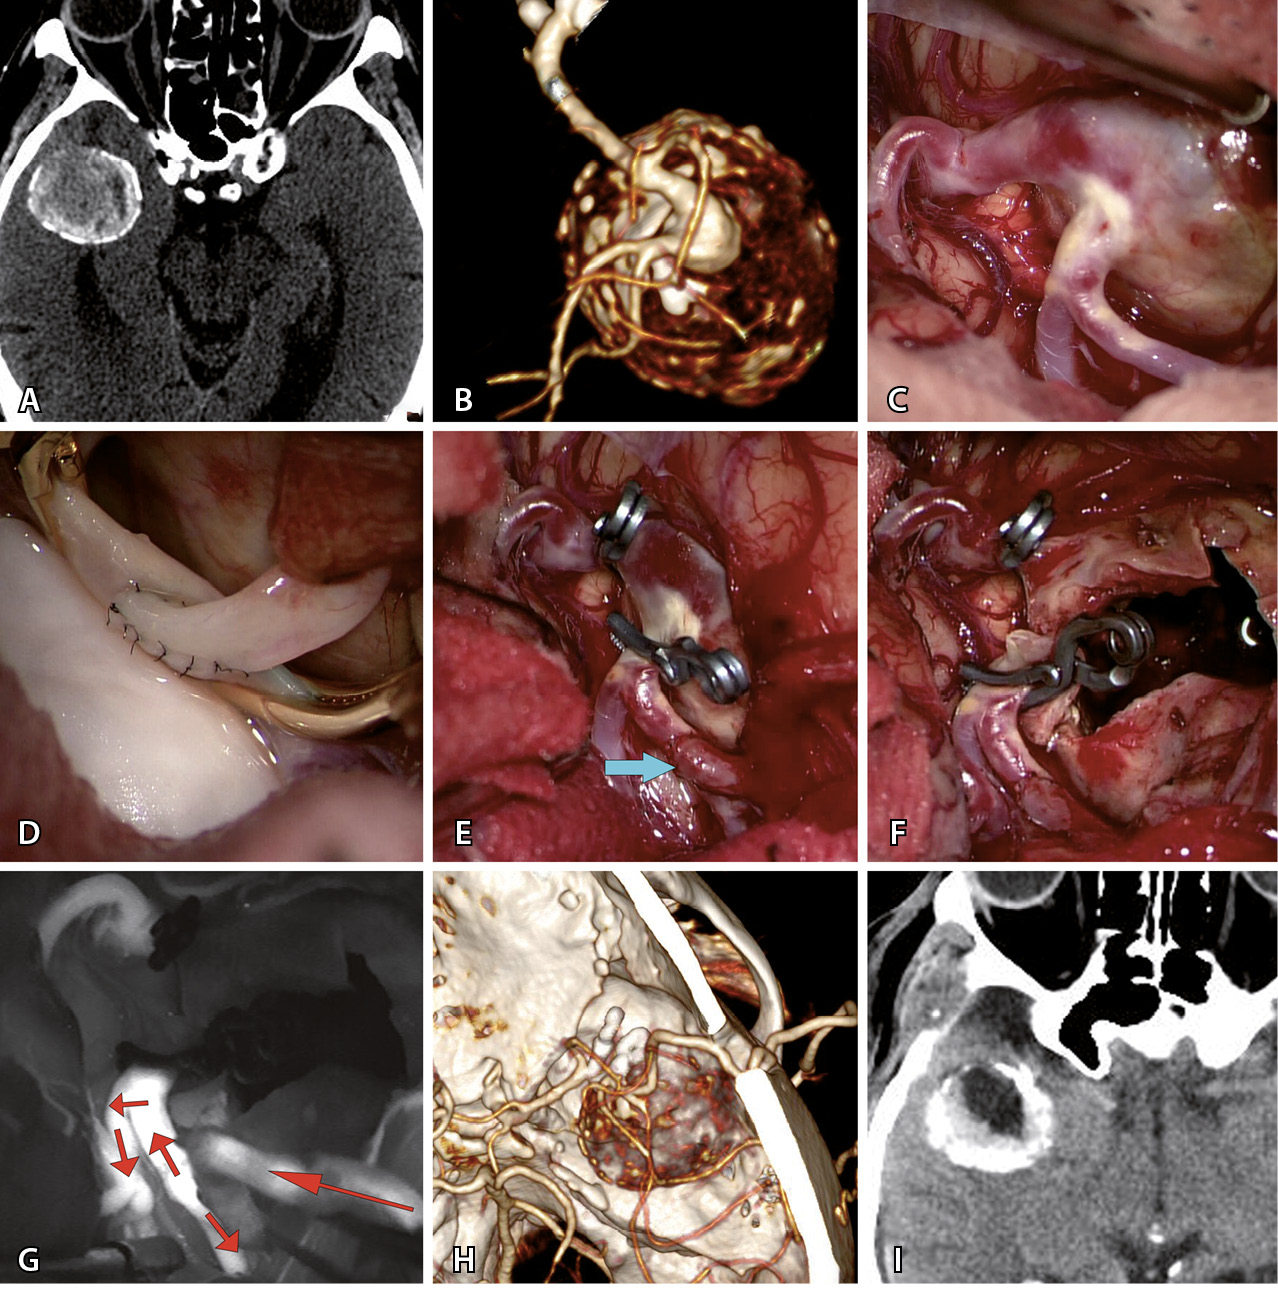

Рис. 2. Треппинг с тромбэктомией гигантской фузиформной частично тромбированной аневризмы М2-сегмента средней мозговой артерии (СМА) после создания экстра-интракраниального микроанастомоза у пациента Т., 69 л. А – компьютерная томография до операции: определяется гигантская частично тромбированная аневризма правой СМА. Б – компьютерная томографическая ангиография (3D) до операции: видна функционирующая часть фузиформной частично тромбированной аневризмы М2-сегмента правой СМА. В – интраоперационное фото: вид аневризмы после препаровки сильвиевой щели. Г – анастомоз между поверхностной височной артерией и М2-сегментом СМА. Д – треппинг аневризмы (стрелкой указан анастомоз). Е – вид аневризмы после тромбэктомии из ее полости. Ж – флюоресцентная видеоангиография: видно хорошее контрастирование шунта через анастомоз и заполнение М2-ветвей (стрелками указано направление кровотока). З – компьютерная томографическая ангиография (3D) после операции: аневризма не контрастируется и хорошо заполняется экстра-интракраниальный анастомоз. И – компьютерная томография головы после операции